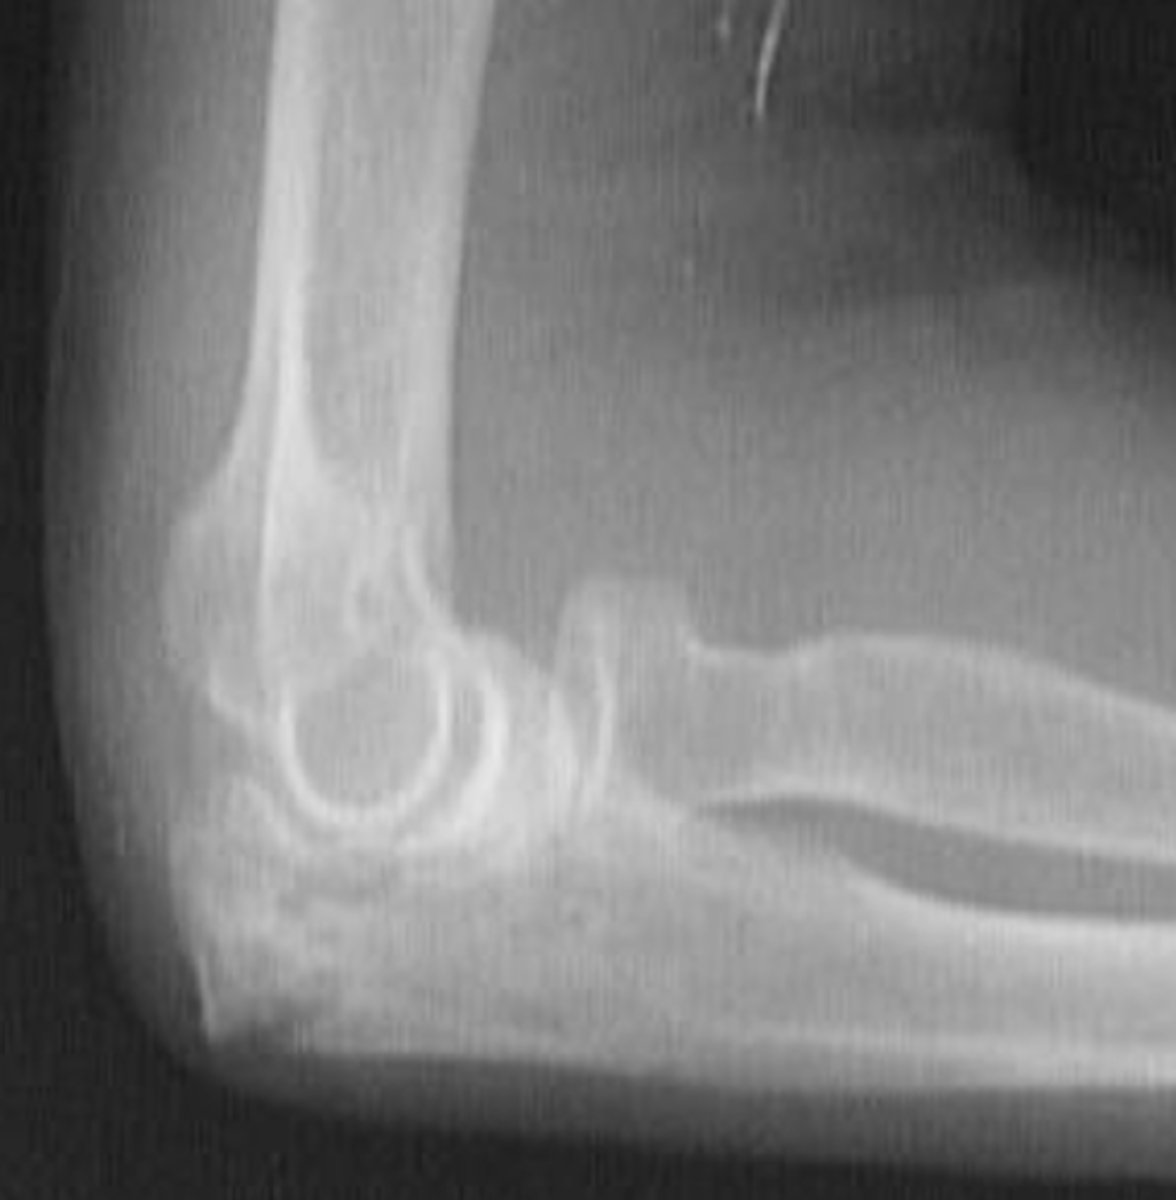

Medial epicondyle avulsion fracture

What is the issue?

AP internal oblique elbow

What view is this?